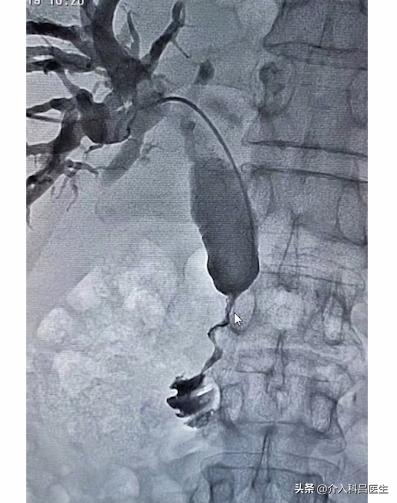

我们经皮肝穿,在腰旁扎个针,直接就扎到肝脏里面,直接就能进到胆管里面。这是我们的造影,可以看到胆管都是扩张的,胆总管也是明显扩张的。

肿瘤侵犯的地方,把胆管给侵犯压迫了,胆汁都淤积在里面,人就成“小黄人”了。于是我们在肿瘤地方放了支架,考虑病人的情况,我们放置的国产支架,非常便宜。支架张开,胆汁就可以顺着支架进入了小肠里面,胆汁还能够参与消化。